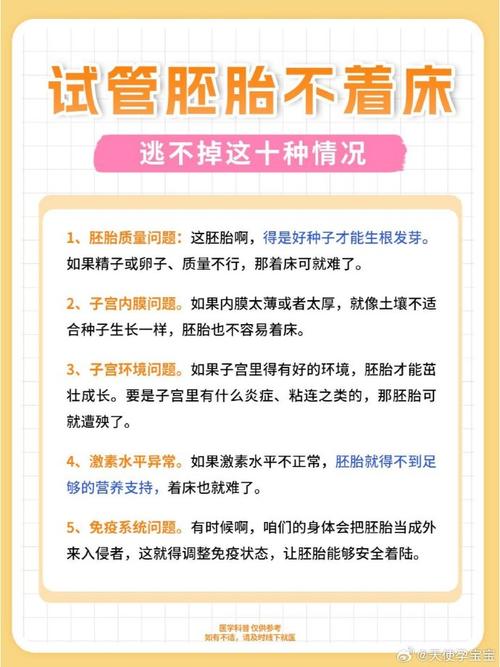

试管婴儿过程中没着床胚胎的原因与解决方案探讨

本文深入探讨了试管婴儿过程中胚胎不着床的原因,包括胚胎自身、子宫、免疫和心理等因素,并列举相关数据说明影响程度。同时,针对这些因素提出了具体的解决方案,助力提高胚胎着床成功率。

试管婴儿着床失败的原因及解决方案

本文详细介绍了试管婴儿着床失败的原因,包括胚胎、子宫、内分泌、免疫等因素,同时针对这些原因给出了相应的解决方案,为面临此困扰的家庭提供了专业的知识和方向。

“试管婴儿7天不着床的原因及解决方法揭秘”

本文详细揭秘试管婴儿7天不着床的原因,涵盖胚胎、子宫内膜、免疫及心理等因素,并针对这些原因给出相应解决方法,助力有需求的家庭更好应对试管婴儿过程中的难题。

试管婴儿多次着床失败的可能原因及解决方案

本文详细探讨了试管婴儿多次着床失败的可能原因,包括胚胎、子宫、免疫、内分泌等因素,并针对这些原因给出了具体的解决方案,旨在帮助有需要的家庭找到应对方法,实现生育梦想。